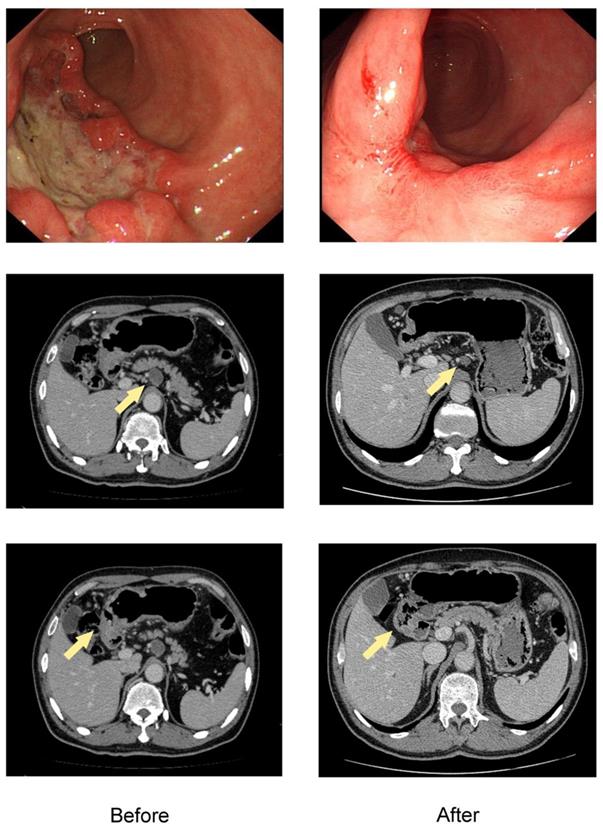

A total of 637 patients diagnosed with gastric adenocarcinoma were retrospective selected in China National Cancer Center database. Of these, 122 patients with initially unresectable gastric cancer treated with systemic chemotherapy followed by curative intent resection met all the inclusion criteria (Figure 1). The median age was 56 years (range 28-78), and there were 88 males (72.1%). The clinicopathological characteristics at initiation of treatment were shown in Table 1. The endoscopic and CT images of the representative patient treated with conversion therapy were shown in Figure 2.

Figure 2

The endoscopic and CT images of the representative patient treated with conversion therapy. Baseline (left) and after 4 cycles of SOX chemotherapy (right) of the primary tumor and ERLN. The lesion of this patient was initially defined as unresectable due to ERLN+. The shrinkage was obtained both in the primary tumor and ERLN and the response was considered to be a PR, which was confirmed by the RECIST criteria.